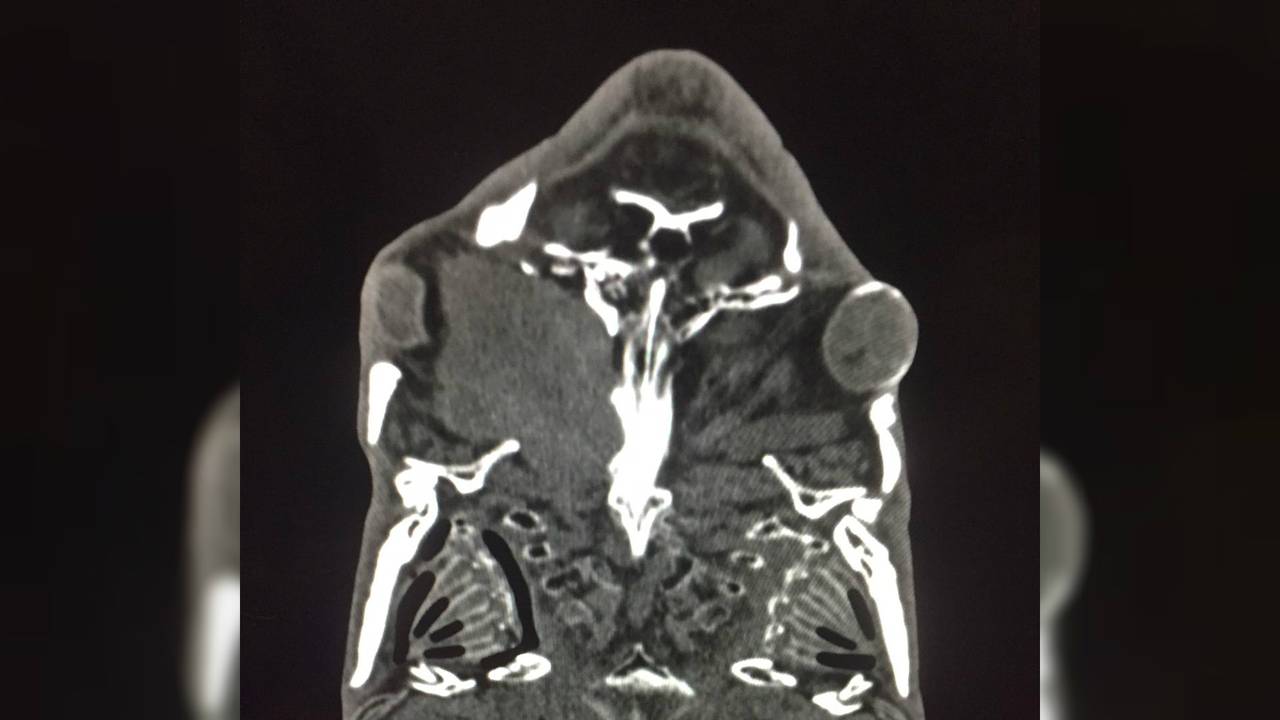

De karper zwom al een tijdje rond met een dik oog. Zijn baasje maakte zich zorgen en nam contact op met dierenarts Rob. Hij heeft zelf geen CT-scan in zijn praktijk, maar wist een kliniek waar er wel een is. De diagnose was niet best: Rob zag een massa die de schedel en de mondholte van het geschubte dier binnendringt.

Een vis onder de scan is niet iets wat dagelijks gebeurt. “Dit is de derde keer dat ik het meemaak. De vis gaat eerst in een bak water met narcosemiddelen erin. Dan is het wachten totdat hij mee gaat werken en dan kun je hem zo onder de scan leggen.”

Een vis kan dus blijkbaar best wel lang op het droge. “Twintig minuten kan wel hoor.” Toen de scan klaar was, ging het dier weer in een bak vers water en werd hij langzaam weer ‘wakker’.